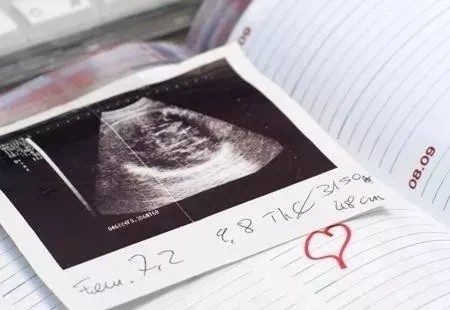

所以怀孕35天左右可以测到孕囊(月经周期短的也可以看到卵黄囊了),如果位置也正确的话,那就可以确定是宫内孕了。

到怀孕42天以后,也就是孕6-7周时,可以看到胎芽和胎心。